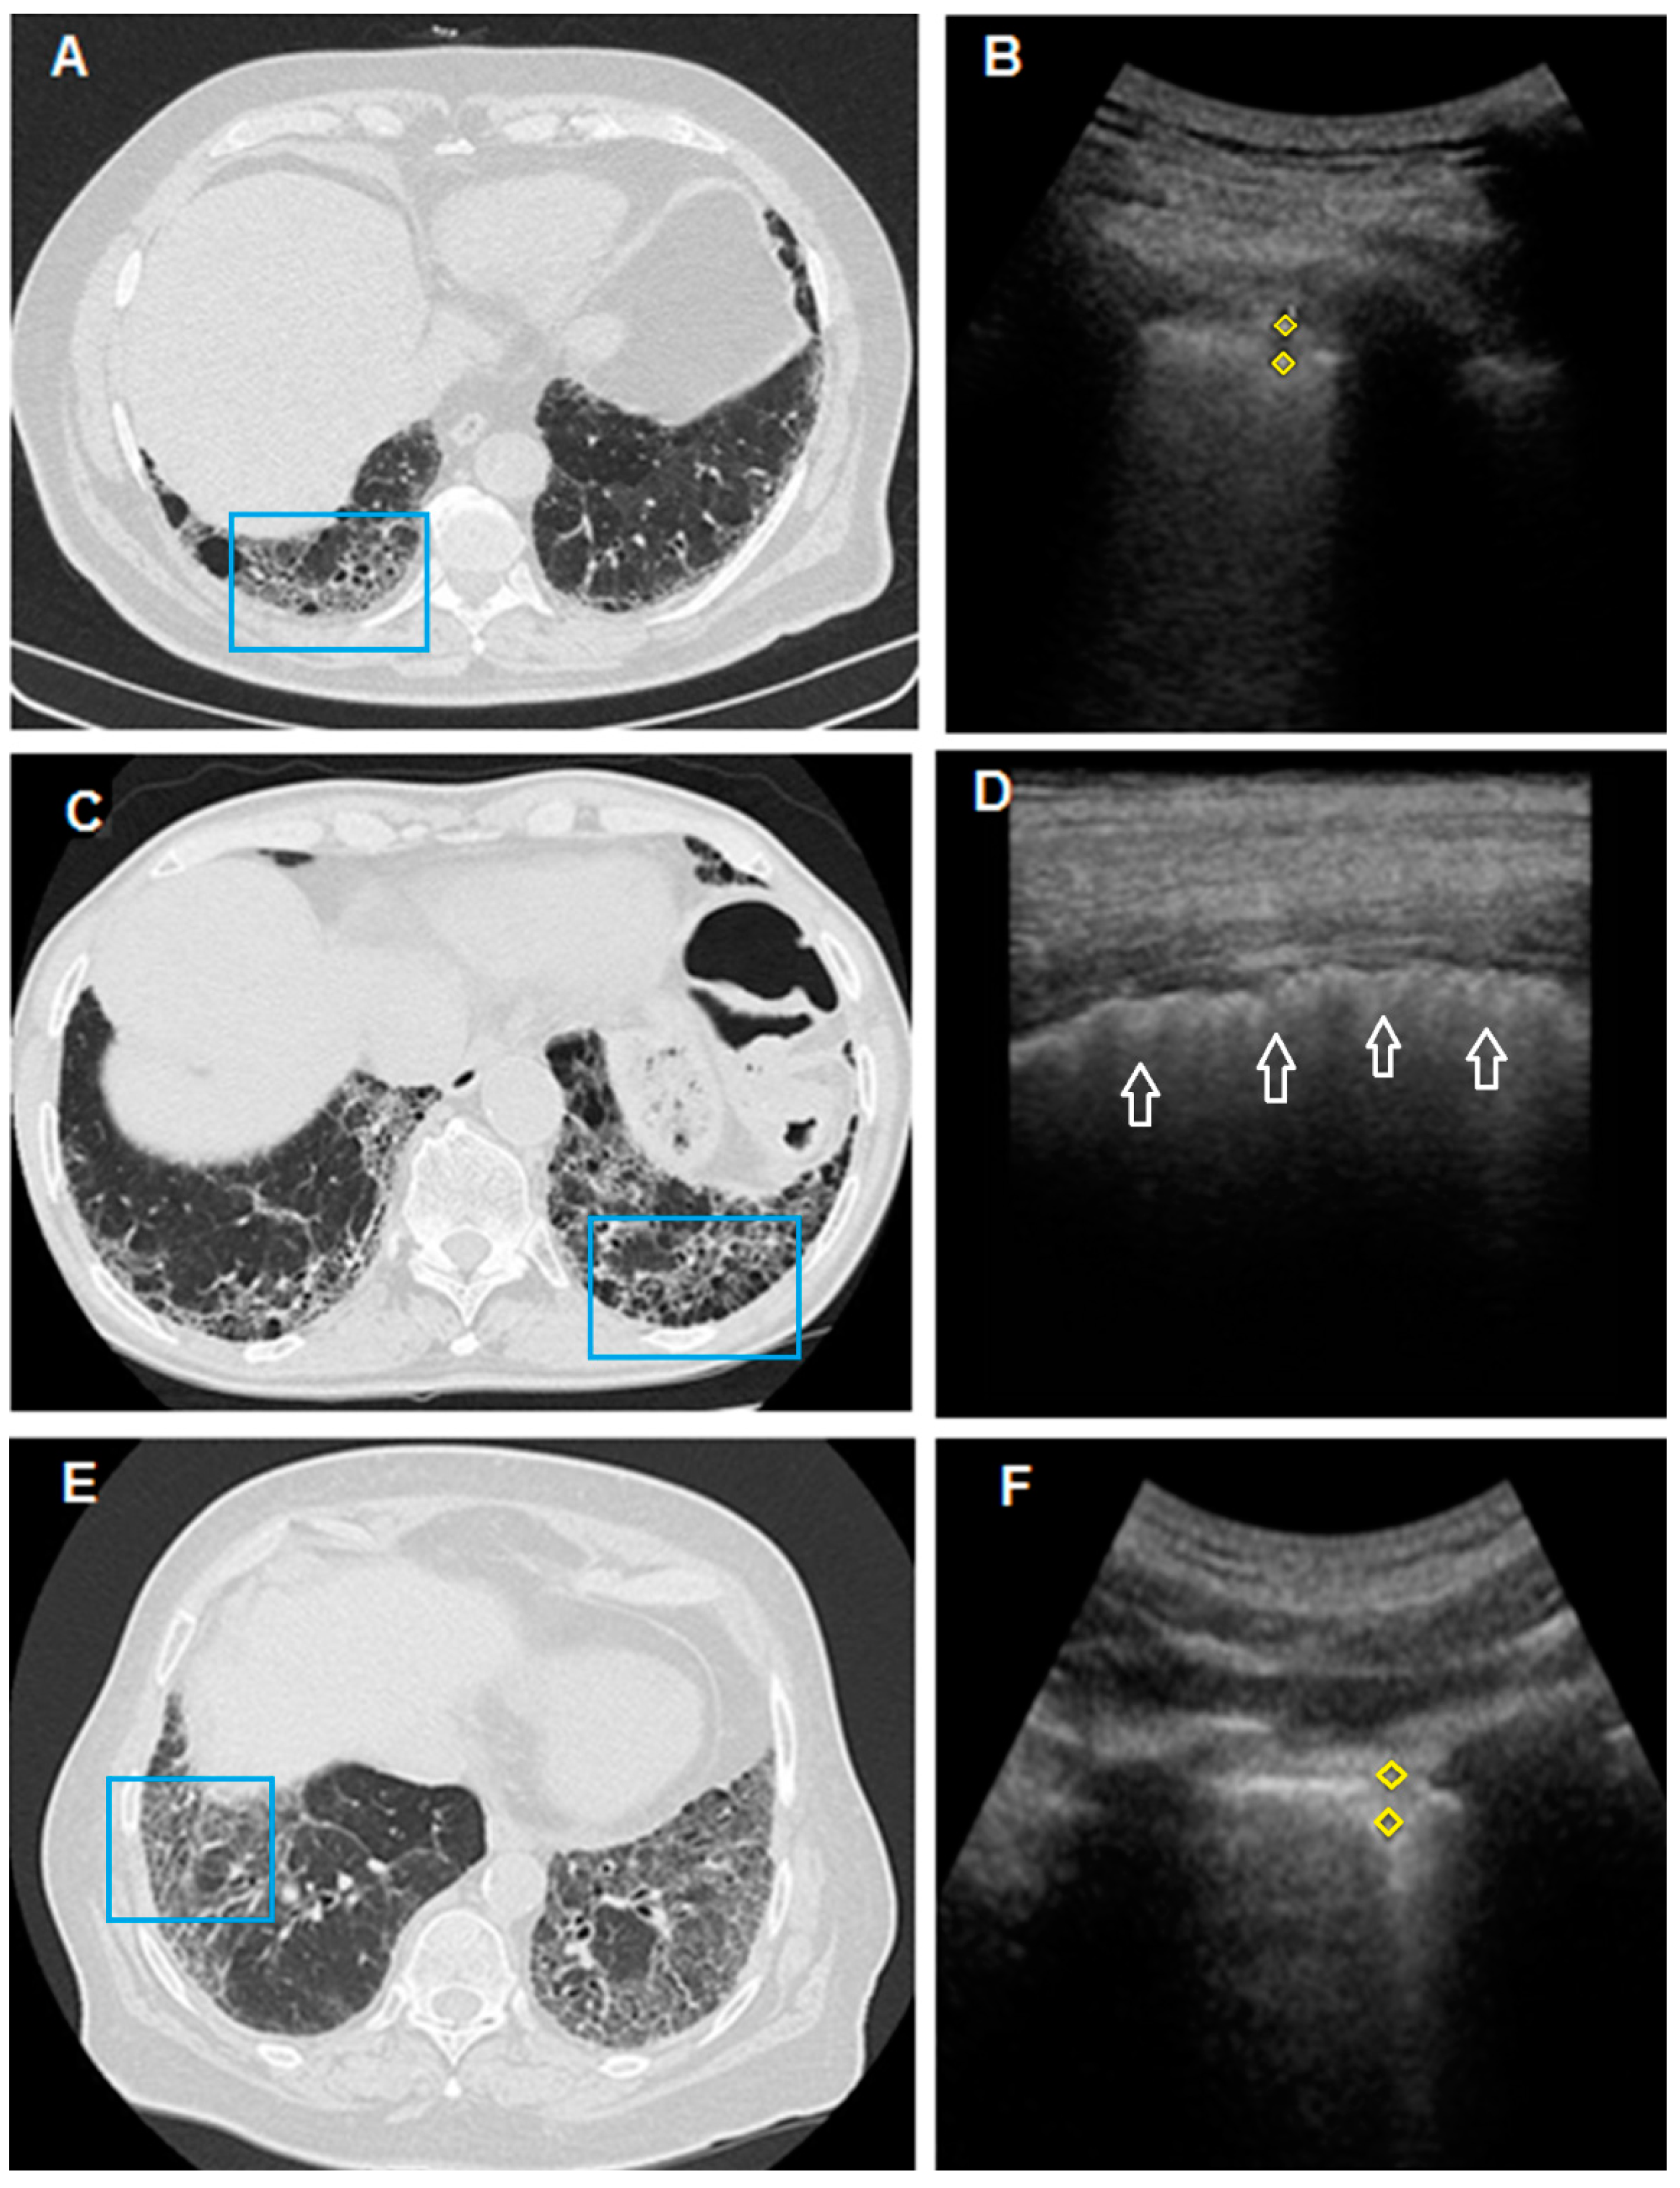

| HRCT patterns, n (%) | |

| Honeycombing | 32 (75%) |

| No Honeycombing | 11 (25%) |

| Predominant Ground Glass | 5 (12%) |

| Predominant Honeycombing | 28 (65%) |

| Mixed | 10 (23%) |

| Ultrasound findings, n (%) | |

| Thickness of the pleural line (>3 mm) | 43 (100%) |

| Irregular/fragmented/blurred pleural line | 42 (98%) |

| >3 B-lines | 38 (86%) |

| Subpleural nodes | 32 (74%) |